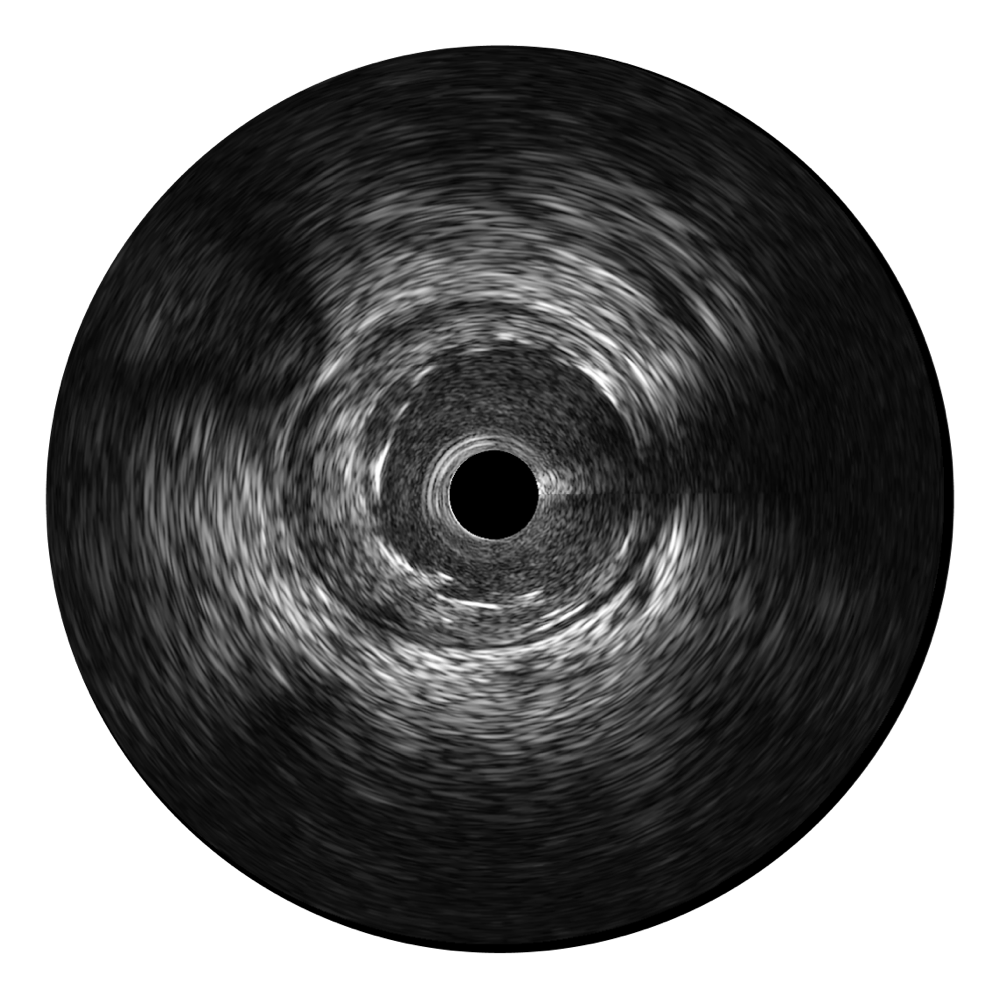

百老汇电子游戏官网宽频IVUS图像

传统IVUS图像

对比传统IVUS导管成像,百老汇电子游戏官网宽频IVUS图像的近场支架梁显影更细腻,远场中膜外血管仍清晰可辨,兼顾远中近,兼顾分辨力与穿透深度